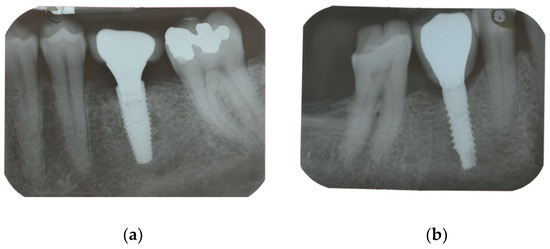

| Secondary Outcome | Marginal bone loss (MBL) | Marginal bone level changes were assessed using intraoral digital periapical radiographs at implant placement (baseline), and at after one year on function. Intraoral radiographs were taken with the parallel technique with customized holder. All the radiographs were evaluated under routine conditions. The software has been calibrated for every single image using the known distance of the implant diameter or length. The distance from the reference point at the implant neck to the first bone to implant contact were taken as the horizontal marginal bone level at both mesial and distal aspects. The average radiographic values of mesial and distal measurements were taken for each implant. Variation of the marginal bone levels at different time was taken as marginal bone loss. |

| Implant placement | 0.04 ± 0.06 (0.00 to 0.07); n = 15 | 0.01 ± 0.02 (0.00 to 0.02); n = 15 | 0.128 |

| One-year follow-up | 0.99 ± 0.71 (0.61 to 1.36); n = 14 | 0.65 ± 0.48 (0.40 to 0.91); n = 13 | 0.166 |

| Difference | 0.96 ± 0.72 (0.58 to 1.34) | 0.65 ± 0.48 (0.40 to 0.90) | 0.192 |